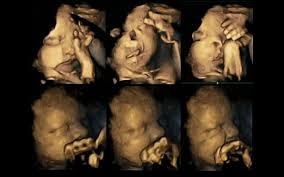

Εναν συγκλονιστικό τρόπο για να αναδείξουν τις βλαβερές συνέπειες του καπνίσματος για τα έμβρυα βρήκαν οι επιστήμονες: τις κινήσεις ενόχλησης που κάνουν με τα μικροσκοπικά τους χέρια τα ίδια τα έμβρυα, όπως αυτές εικονίζονται σε υπερηχογραφήματα με τετραδιάστατη απεικόνιση (4D).

Η δρ Νάντια Ρέισλαντ, από το Πανεπιστήμιο του Ντάραμ, στη Βορειοανατολική Αγγλία, έχει καταγράψει χιλιάδες μικροσκοπικές κινήσεις εμβρύων κατά την πολυετή πείρα της στα 4D υπερηχογραφήματα. Για τις ανάγκες τις έρευνας παρακολούθησε 20 μητέρες στο Πανεπιστημιακό Νοσοκομείο James Cook του Μίντλεσμπρο, τέσσερις εκ των οποίων κάπνιζαν περίπου 14 τσιγάρα τη μέρα.

Επειτα από ενδελεχή μελέτη των υπερηχογραφημάτων τους κατά την 24η, την 28η, την 32η και την 36η εβδομάδα της κύησης, παρατήρησε ότι τα έμβρυα των οποίων οι μητέρες κάπνιζαν έκαναν πολύ περισσότερες επαναλαμβανόμενες κινήσεις με το στόμα τους ή άγγιζαν τον σώμα τους απ’ ό,τι τα έμβρυα των οποίων οι μητέρες δεν κάπνιζαν. Συνήθως τα έμβρυα κουνούν λιγότερο το στόμα τους και αγγίζουν το σώμα τους κατά τις τελευταίες εβδομάδες της κύησης.